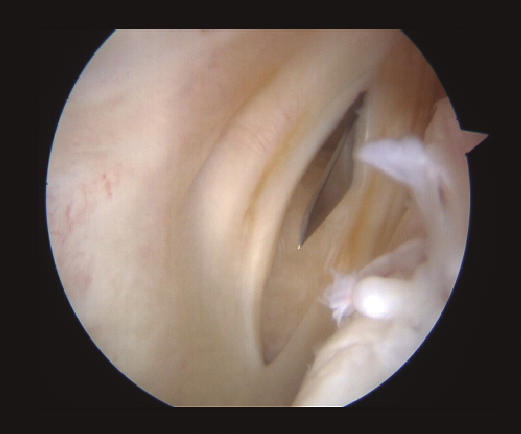

Figura 1. Visión a través del intercóndilo de lesión inferior oculta, que se detecta con la palpación a través del portal posteromedial.

Aunque no se aprecien signos de inestabilidad meniscal desde una visión anterior, se realiza de forma sistemática una exploración del segmento posterior. Se realiza sistemáticamente una exploración visual del compartimento PM a través de la escotadura intercondílea, con flexión de rodilla de 90°. El artroscopio es introducido por el portal AL en el triángulo formado por el cóndilo medial, el ligamento cruzado posterior y la espina tibial. Tras introducir el artroscopio en este espacio, podemos avanzarlo hacia posterior sobre el borde del cóndilo, realizando un valgo forzado primero en flexión y luego en extensión. La rotación interna de la tibia puede ayudarnos en la visualización. Este gesto subluxa el platillo tibial posterior y produce una traslación posterior del tercio medio del platillo tibial. Con esta maniobra se pueden visualizar dos tercios de las lesiones periféricas que vayan desde el segmento posterior hasta el segmento medio. En caso de desgarros del segmento posterior, se realiza un portal PM (Figura 2). Mediante transluminación, el cirujano puede observar las estructuras vasculares y nerviosas de la zona para realizar el portal con seguridad. El punto de introducción de la aguja se sitúa proximal a los isquiotibiales, 1 cm posterior a la interlínea articular femorotibial medial. La rodilla se flexiona a 90° para evitar daños en el paquete poplíteo. La aguja se introduce de fuera a dentro en la dirección de la lesión.